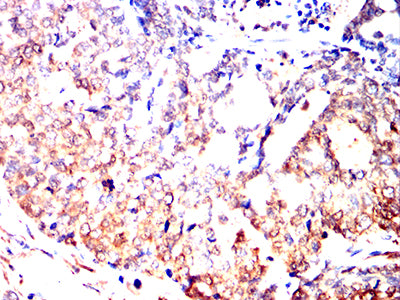

Immunohistochemical analysis of paraffin-embedded mouse brain tissues using UCHL1 mouse mAb with DAB staining.

Immunohistochemical analysis of paraffin-embedded mouse kidney tissues using UCHL1 mouse mAb with DAB staining.